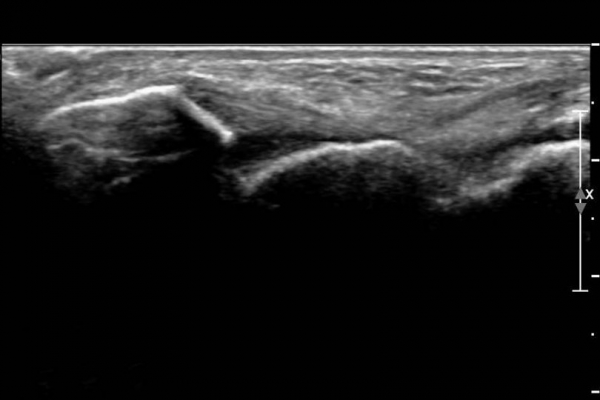

¾Õ°æ°ñºñ°ñÀδë Á¾´Ü¸é°Ë»ç¿¡¼­ °æ°ñºñ°ñÀδëÀÇ  Àú¿¡ÄÚ  ºÎÁ¾ ¹× ÀδëºÎÂøºÎ °æ°ñÀÇ

°ß¿­°ñÀýÀÌ  °üÂûµÊ(»çÁø 2, 3, 4)